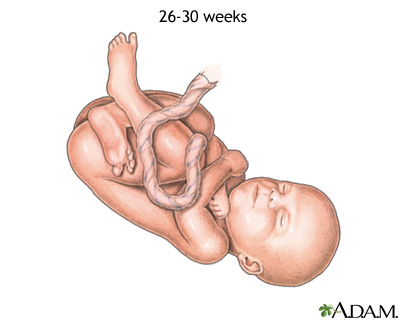

Week 26

- Eyebrows and eyelashes are well-formed.

- All parts of your baby's eyes are developed.

- Your baby may startle in response to loud noises.

- Footprints and fingerprints are forming.

- Air sacs form in your baby's lungs, but lungs are still not ready to work outside the womb.

Weeks 27 to 30

- Your baby's brain grows rapidly.

- The nervous system is developed enough to control some body functions.

- Your baby's eyelids can open and close.

- The respiratory system, while immature, produces surfactant. This substance helps the air sacs fill with air.